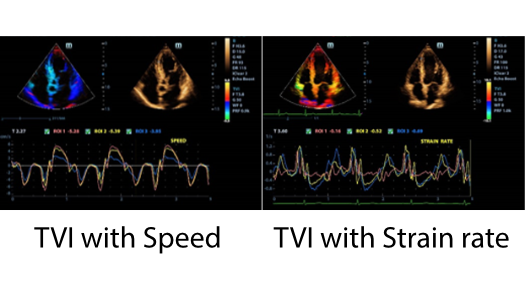

MX7? ??? ZST+ ???? ???? ??? ??? ???? ?? ??? ?? ??? ??? ??? ?? ???? ?? ???? ?????? ?????. ??? ?? ??? ?? 8??? ??? ??? ?? ?? ??? ?? ???? ??? ?????. ?? ?? ? ?? ??? ?? ??? ??? ? ????.